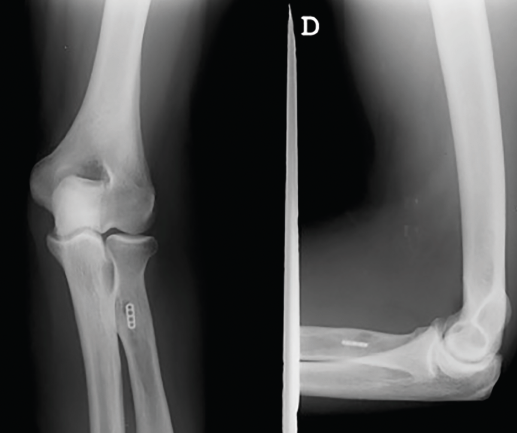

Es recomendable anclar primero el injerto a nivel distal, ya que facilita encontrar la tensión adecuada de la sutura a nivel proximal, que se recomienda realizar aproximadamente a unos 45-60° de flexión del codo (Figura 4).

Figura 4. Anclaje monocortical endomedular del botón cortical (EndoButton®, S&N).